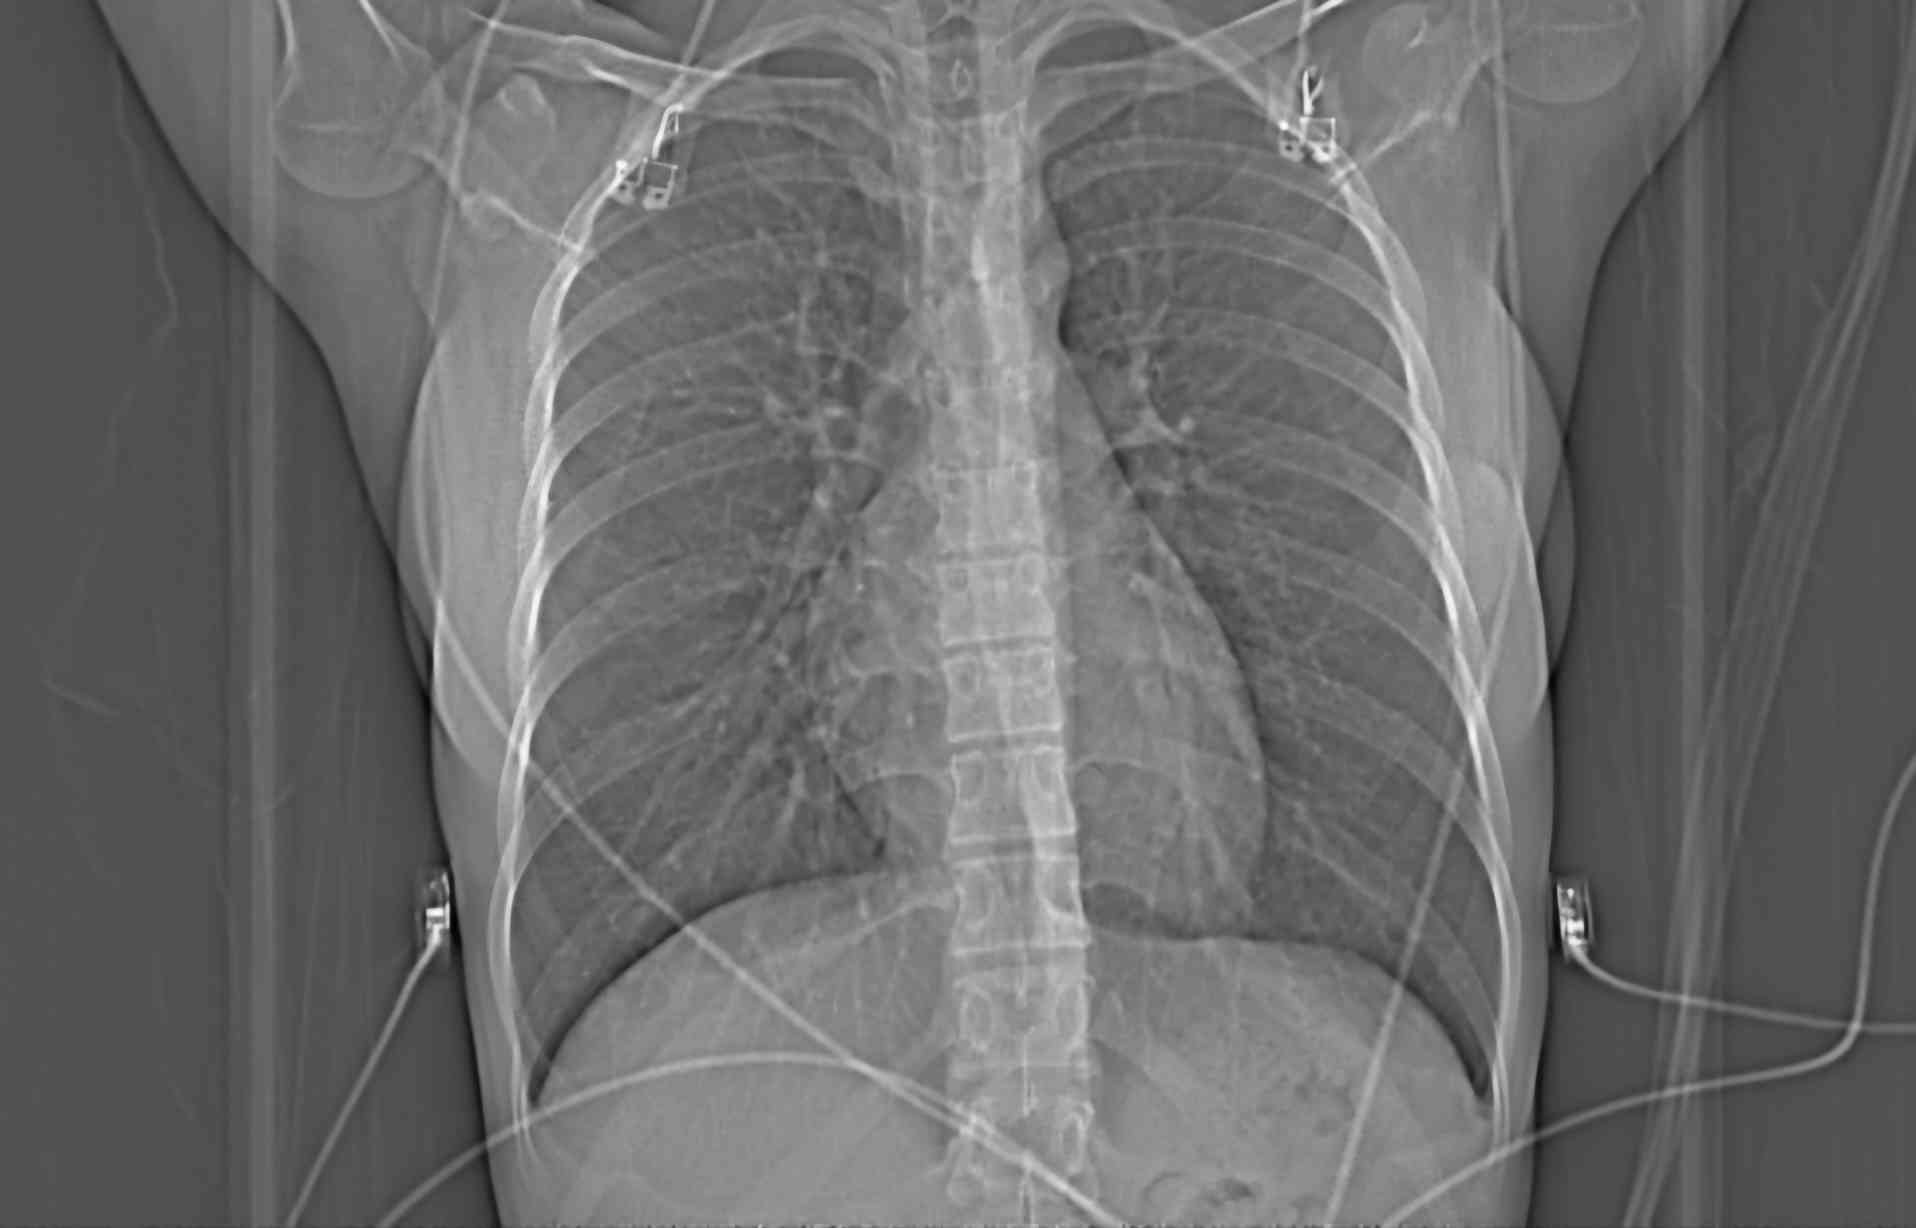

Since I got heart surgery a month ago, I can hear my heart beating all the time. Apparently it’s normal. I read online that they proved it wasn’t psychosomatic by performing open heart surgery on dogs and measuring the sound of their heartbeats afterwards. They found that dogs split open on the operating table -> dogs that hear their own heartbeat all the time. I also read that some dogs have a resting heart rate of over 200bpm. Woof woof woof. They’ve had me on gabapentin for a second now. It makes me feel so stupid like I got a lobotomy. I kept imagining a surgeon covered in dog guts. Woof… I wonder if my cardiologist knows about that study. I’m in the waiting room to see him now. I don’t think he would believe me about my symptoms unless I told him a dog experienced it too. Maybe that would be a more reliable source to him. It took so long to even get a referral to a cardiologist. I started noticing symptoms when I was 16, my mom noticed too in my behavior. She took me to the doctor. A lot of girls your age can misinterpret period cramps as chest pain, or it could be painful breast growth. Have you noticed your breasts getting larger? Actually, the new primary care I switched to said basically the same thing. It took 3 years of mentioning it at every appointment with multiple doctors for them to finally refer me to a cardiologist, who then told me the exact same thing again. At least he ordered some tests, surely with the intention to prove that I was making it up, give me a psych rec, etc, but they all came back abnormal. I thought that getting proof of my condition would stop my cardiologist from being so condescending, but being wrong wounded his ego or something. He treats me like I wanted this outcome just to rub his face in it. Yes, you technically do have a heart condition, that I found, that I diagnosed. Don’t forget who’s the doctor here. Just because you read Webmd doesn’t mean you know what you’re talking about. The thing that made me an even bigger nuisance in his eyes was when I wanted to actually go through with surgery, the standard treatment for my diagnosis. I’ve been worried to tell him that I don’t think I’m recovering properly.

The waiting room was small, lit like a clinic in a hospital. It smelled like a perfume I tried in a store while visiting my family in Japan a few years back that was supposed to smell like spinal fluid. I don’t know why I sprayed it on my wrist, the smell made me sick for the rest of the day even after I tried to scrub it off. Who would ever want to smell like that? A few people had been called back before me now, elderly wives shuffled back to the examination rooms with their husbands. A lot of the chatter had died down. Quiet rooms are the worst for me, all I can focus on is the sound of my own heart beating. It sounds sick, like it’s whining with every contraction. Is it really that fast? Anyone that had seen me for the past month must have thought I accidentally superglued my two fingers to my carotid artery. It’s such an awful sound. Highway pileup with 160 new cars crashing into it every minute. I wish everyone could hear this when I walked into a room. Your period’s so loud! haahhhh. Bear down, breathe through pursed lips. That’s what slows it down. I can’t stand it… The gabapentin stops my chest from hurting, but I can still feel it buzzing where it would hurt, I can hear that it hurts. When I eventually have a heart attack, I’m sure I’ll hear it before I feel it. I imagined the sound of a shipping crate being torn in half and then me dying. I’m going to have an echocardiogram later, maybe they’ll catch that sound on the speakers.

I couldn’t help but laugh during my echo, hearing my heartbeat doubled on the speakers made me feel like I was losing my mind. It was painfully long and my chest was sore from how hard the nurse was pushing the probe into me. I was waiting on a bench outside the hospital for my mom to finish some errands she had been running down the street. The sun was shining directly on me, it made me feel woozy but I didn’t want to go back inside. The heat was drying the ECG gel into an awful sticky consistency all over my chest. My shirt kept getting glued to the spot where they spread the gel, I pulled at it and it made a noise as it came unstuck. I listened to birds and my heart.